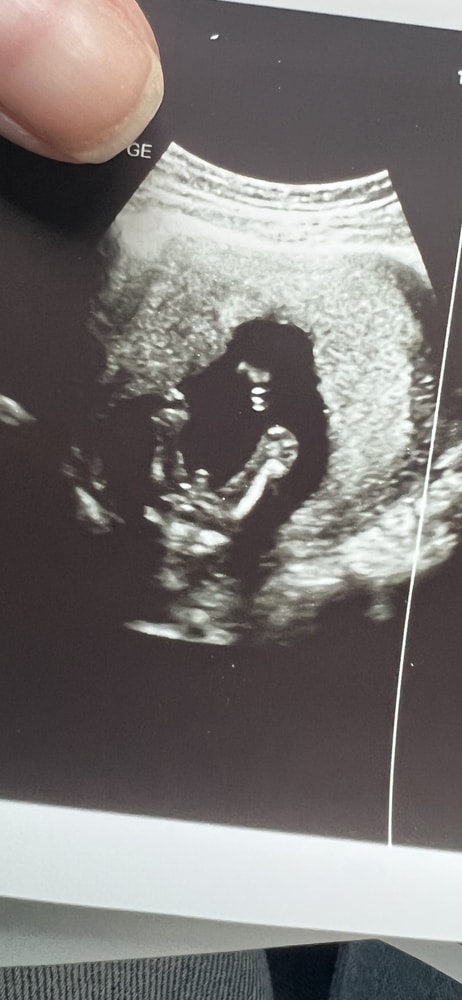

Алла М в Благополучная беременность 3 месяца Тут точно мальчик ? Пол малыша Узистка дала 80 процентов ) 17 недель Посмотрите еще 20 записей на эту тему Лучший ответ Алла М 20.09.2025 Ответить Анастасия Алла М, мне кажется тут явно мальчик) 20.09.2025 Ответить Oks Алла М, это же ножки и посередине пипка. Мне показывали такие же причиндалы в 20 недель) 20.09.2025 Ответить Отменить Ответить Юлия * Мальчик конечно))) 20.09.2025 Ответить Алла М Юлия *, почему она сказала что большая вероятность тогда а не просто Мальчик 20.09.2025 Ответить Юлия * Алла М, потому что всегда остаётся погрешность на пуповину между ног. Если врач был бы не уверен, не стал бы вообще пол предполагать 20.09.2025 Ответить Aza Точно не пуповина )) мальчик у вас. 20.09.2025 Ответить Юлька Согласна с врачом. Тут скорее всего мальчик. Просто с такого ракурса иногда пуповину можно принять за «мальчика». Перестраховывается) 20.09.2025 Ответить Кошка Лена У девочек такой штуки нет🤣 20.09.2025 Ответить Пол малыша в 12 недель Может ли ошибаться анализ на определение Пола плода? Чаты Беременных Выберите чат: Январята-2026 Февралята-2026 Мартята-2026 Апрелята-2026 Майчата-2026 Июнята-2026 Июлята-2026 Августята-2026